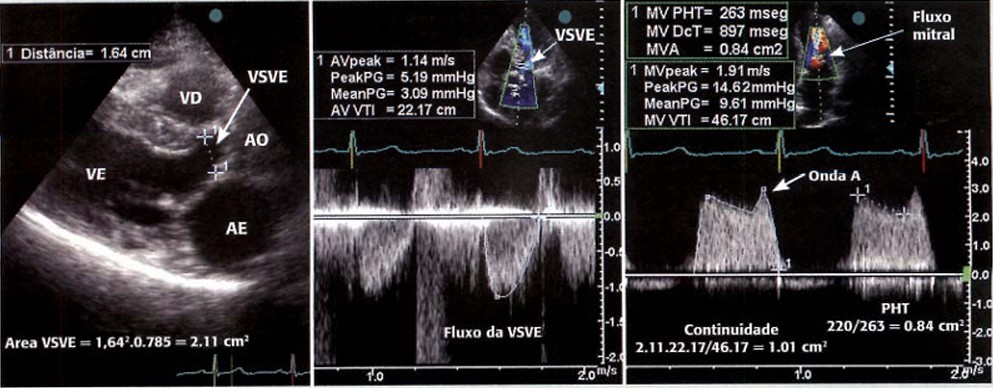

EQUAÇÃO DE CONTINUIDADE:

Em primeiro lugar, deve-se determinar o débito sistólico através da valva aórtica. Mede-se o diâmetro da via de saída do ventrículo esquerdo (VSVE) no eixo paraesternal longitudinal durante a sístole. Depois, calcula-se a área da VSVE a partir da seguinte fórmula: Área = diâmetro VSVE² x 0.785.

Já na janela apical 5C, utiliza-se o Doppler pulsátil e com o volume amostra posicionado imediatamente abaixo do plano valvar aórtico e, a partir do traçado espectral do fluxo da VSVE, mede-se a velocidade integral. Temos, então, o débito sistólico através da fórmula “Débito Sistólico = área de VSVE x VTI VSVE“.

Depois, no traçado espectral do fluxo mitral, mede-se a velocidade integral. A partir daí, podemos calcular a área valvar através da fórmula “Área Valvar Mitral = débito sistólico / VTI mitral“.

Em pacientes que apresentam ritmo de FA, taquiarritmias e bloqueio atrioventricular de primeiro grau, recomenda-se calcular a área valvar mitral pela equação de continuidade. Este método também está indicado nas aferições da área mitral realizadas logo após a realização de valvotomia mitral, em que o edema das cúspides observado após o procedimento pode interferir na medicação pelo método PHT.